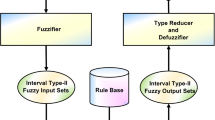

Investigation of brain cancer can detect the abnormal growth of tissue in the brain using computed tomography (CT) scans and magnetic resonance (MR) images of patients. The proposed method classifies brain cancer on shape-based feature extraction as either benign or malignant. The authors used input variables such as shape distance (SD) and shape similarity measure (SSM) in fuzzy tools, and used fuzzy rules to evaluate the risk status as an output variable. We presented a classifier neural network system (NNS), namely Levenberg–Marquardt (LM), which is a feed-forward back-propagation learning algorithm used to train the NN for the status of brain cancer, if any, and which achieved satisfactory performance with 100% accuracy.

The proposed methodology is divided into three phases. First, we find the region of interest (ROI) in the brain to detect the tumors using CT and MR images. Second, we extract the shape-based features, like SD and SSM, and grade the brain tumors as benign or malignant with the concept of SD function and SSM as shape-based parameters. Third, we classify the brain cancers using neuro-fuzzy tools. In this experiment, we used a 16-sample database with SSM (μ) values and classified the benignancy or malignancy of the brain tumor lesions using the neuro-fuzzy system (NFS).

We have developed a fuzzy expert system (FES) and NFS for early detection of brain cancer from CT and MR images. In this experiment, shape-based features, such as SD and SSM, were extracted from the ROI of brain tumor lesions. These shape-based features were considered as input variables and, using fuzzy rules, we were able to evaluate brain cancer risk values for each case. We used an NNS with LM, a feed-forward back-propagation learning algorithm, as a classifier for the diagnosis of brain cancer and achieved satisfactory performance with 100% accuracy. The proposed network was trained with MR image datasets of 16 cases. The 16 cases were fed to the ANN with 2 input neurons, one hidden layer of 10 neurons and 2 output neurons. Of the 16-sample database, 10 datasets for training, 3 datasets for validation, and 3 datasets for testing were used in the ANN classification system. From the SSM (µ) confusion matrix, the number of output datasets of true positive, false positive, true negative and false negative was 6, 0, 10, and 0, respectively. The sensitivity, specificity and accuracy were each equal to 100%.